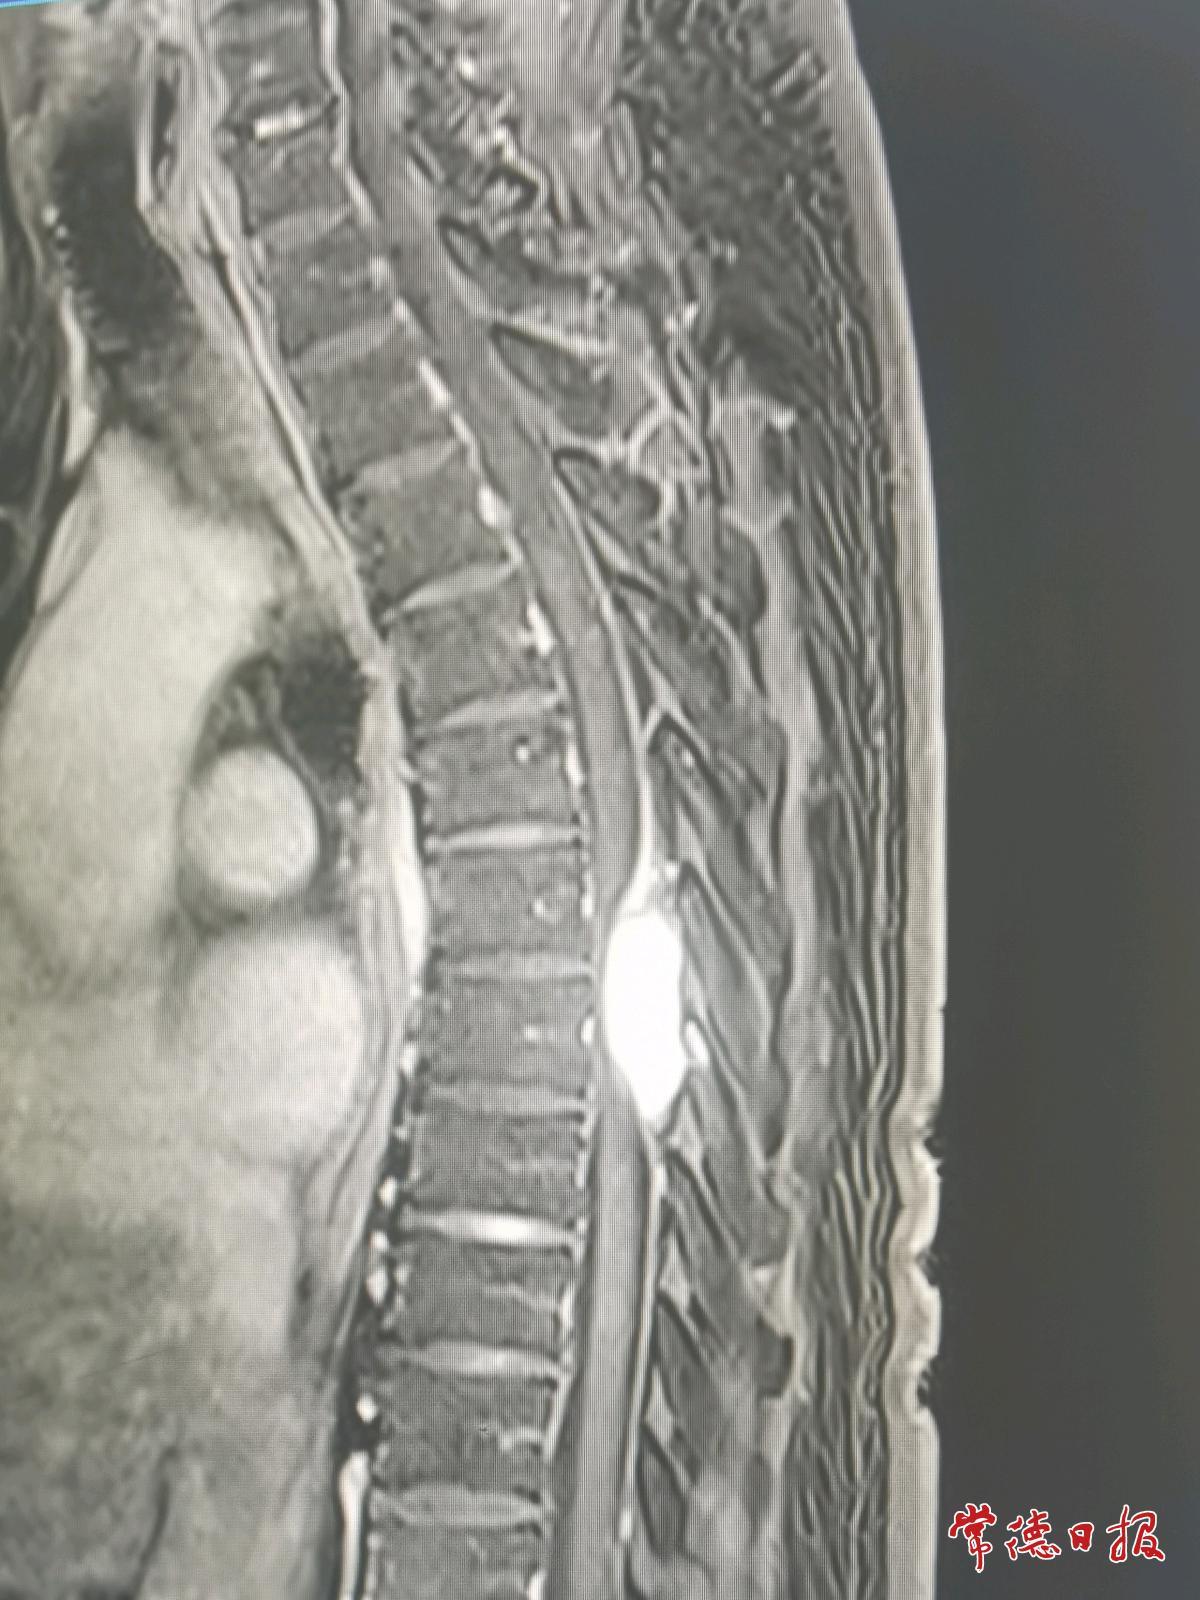

经磁共振检查,医生发现邓伯伯胸6-7椎管内长有一个血管瘤,属于脊髓肿瘤。正是肿瘤压迫神经,导致双腿功能逐步“失灵”。

针对邓伯伯的病情,吴孝才团队为其施行了显微镜下椎管内肿瘤切除术。手术切口小、创伤小,显微镜下可放大4至10倍,清晰显示肿瘤与周围组织的关系。术后经康复治疗,邓伯伯双下肢麻木、疼痛及肿胀基本消失,佩戴支具后可自主行走,生活基本自理。